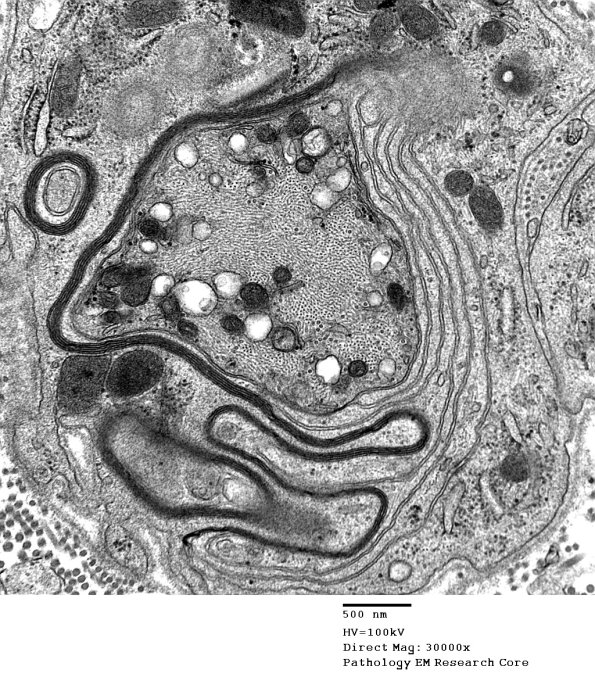

A complex non-compacted myelin sheath, evidence of remyelination. (electron micrographs)